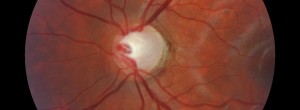

Glaucoma_Nervioptic1_PORTADA

· 02/07/2014

Prospective, randomised, placebo-controlled, double-masked, three-armed, multicenter Phase II/III trial to establish the safety and efficacy of a topical treatment of Neovascular Glaucoma